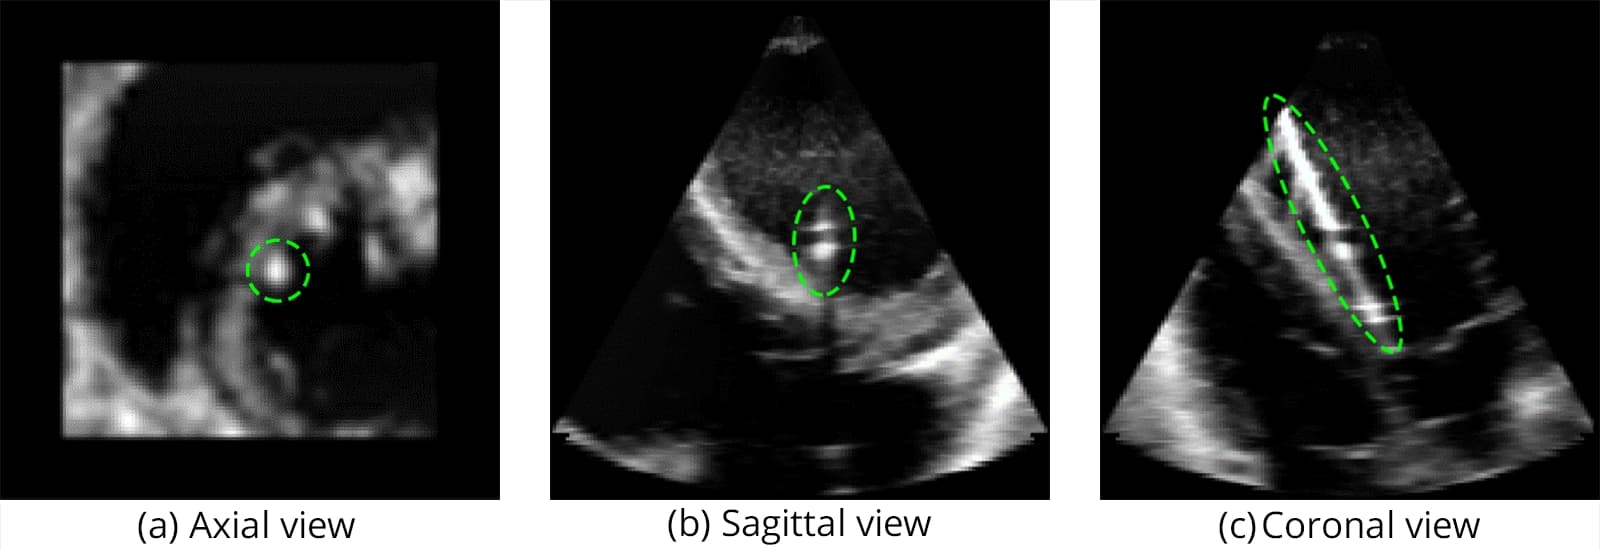

The catheter used in this study is shown in Figure 1, while Figure 2 illustrates the challenging visibility of catheters in raw ultrasound data.